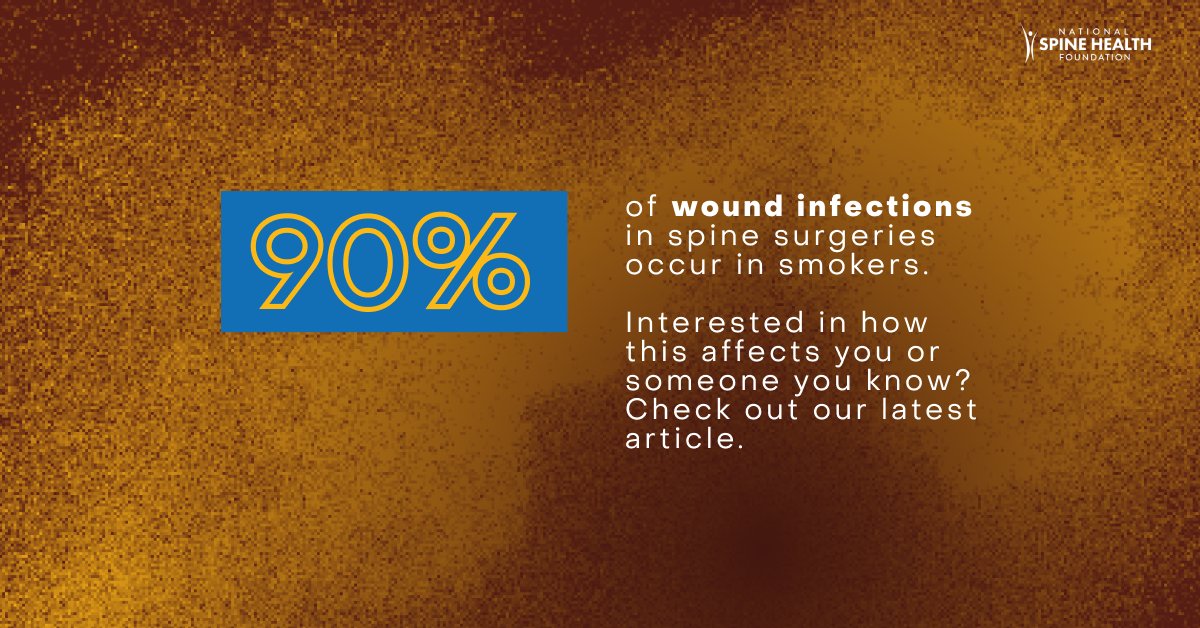

Research finds several factors contribute to low back disc problems: ✅ Increased body mass index (BMI) ✅ Sedentary behavior ✅ Smoking ✅ Disruptions in sleep We can help! #lowback #spinaldisc #chiropractic Source: Liu, et al. Journal of Orthopaedic Research. July 2023.

A new study found that several factors contribute to low back disc problems: ✅ Increased body mass index (BMI) ✅ Sedentary behavior ✅ Smoking ✅ Disruptions in sleep youtube.com/embed/HzeWQYQc… #lowback #spinaldisc #chiropractic

#GlobalSpineJournal reports that smokers are more prone to back pain and #SpinalDisc problems. #Smoking aggravates neck and lower back disc degeneration and complicates spinal surgeries. Curious about the impact? Read our latest article: spinehealth.org/article/smokin…

A new study found that several factors contribute to low back disc problems: ✅ Increased body mass index (BMI) ✅ Sedentary behavior ✅ Smoking ✅ Disruptions in sleep youtube.com/embed/HzeWQYQc… #lowback #spinaldisc #chiropractic

Research finds several factors contribute to low back disc problems: ✅ Increased body mass index (BMI) ✅ Sedentary behavior ✅ Smoking ✅ Disruptions in sleep We can help! #lowback #spinaldisc #chiropractic Source: Liu, et al. Journal of Orthopaedic Research. July 2023.

Research finds several factors contribute to low back disc problems: ✅ Increased body mass index (BMI) ✅ Sedentary behavior ✅ Smoking ✅ Disruptions in sleep We can help! #lowback #spinaldisc #chiropractic Source: Liu, et al. Journal of Orthopaedic Research. July 2023.